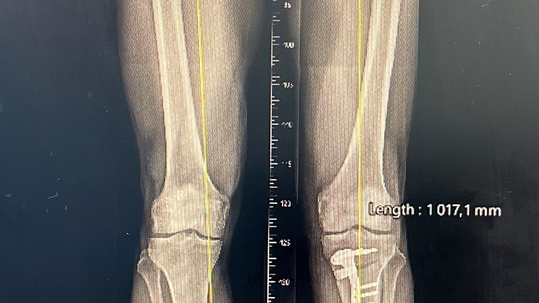

OSTEOTOMIE DOLNÍCH KONČETIN

Princip korekční osteotomie dolní končetiny spočívá ve změně osy nad či pod kolenním kloubem tak, aby jeho zatěžování bylo přemístěno z postižené části kloubu i na část zdravou. S vývojem moderních osteosyntetických materiálů se podařilo docílit velmi dobrých výsledků v kvalitě a rychlosti kostního hojení. To umožnilo v posledních několika letech doslova renesanci operací, jejichž výsledkem je srovnání ideální osy dolních končetin u pacientů, kteří mají, lidově řečeno, „nohy do O nebo do X“. Kromě kosmetického efektu výkon zároveň ochraňuje chrupavku a ostatní struktury uvnitř kloubu a prodlužuje jejich životnost tak, že se pacienti často mohou i vyhnout kloubním náhradám.